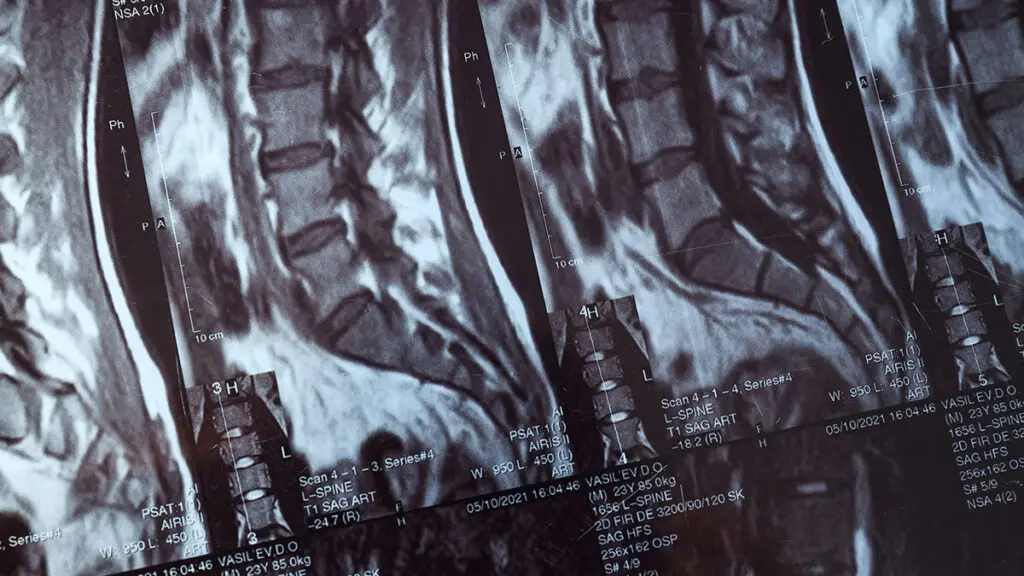

Global Spine Solutions è il centro di neurochirurgia vertebrale di eccellenza a Roma per chirurgia mini invasiva colonna vertebrale. I nostri neurochirurghi eseguono interventi con tecniche mininvasive all'avanguardia, che consentono di minimizzare il trauma chirurgico, ridurre i tempi di degenza e accelerare il recupero funzionale del paziente rispetto alla chirurgia tradizionale.

Ogni procedura di chirurgia mini invasiva colonna vertebrale viene pianificata in modo personalizzato, dopo un'attenta valutazione clinica e strumentale. Il team multidisciplinare di Global Spine Solutions discute ogni caso in collegialità per garantire il miglior risultato possibile, assicurando al paziente un percorso di cura trasparente dalla diagnosi fino alla riabilitazione post-operatoria.